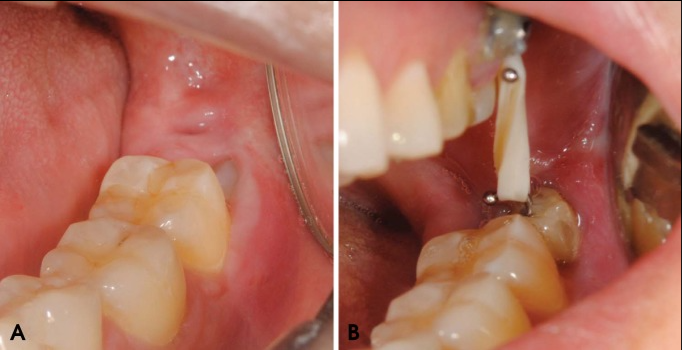

在微型螺钉安装后3周,智齿明显突出(图2),CBCT(图3)证实了这一点。此时,下8被手术取出。牙根没有断裂,下8很容易从牙槽窝中取出。手术期间,没有过度出血或疼痛。临床上未观察到下牙槽神经损伤或暴露。在取出和清洁下8后,通过检查下8观察到与下颌管接触的根部弯曲(图4)。

图2 临床照片显示正畸牵引前 (A) 和牵引后 (B) 下第三磨牙